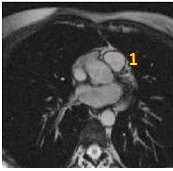

Figure 1. Prescribe right ventricular outflow tract view

2. From the right ventricular outflow tract view, prescribe (blue line indicates graphic location) and acquire a pulmonary valve view.